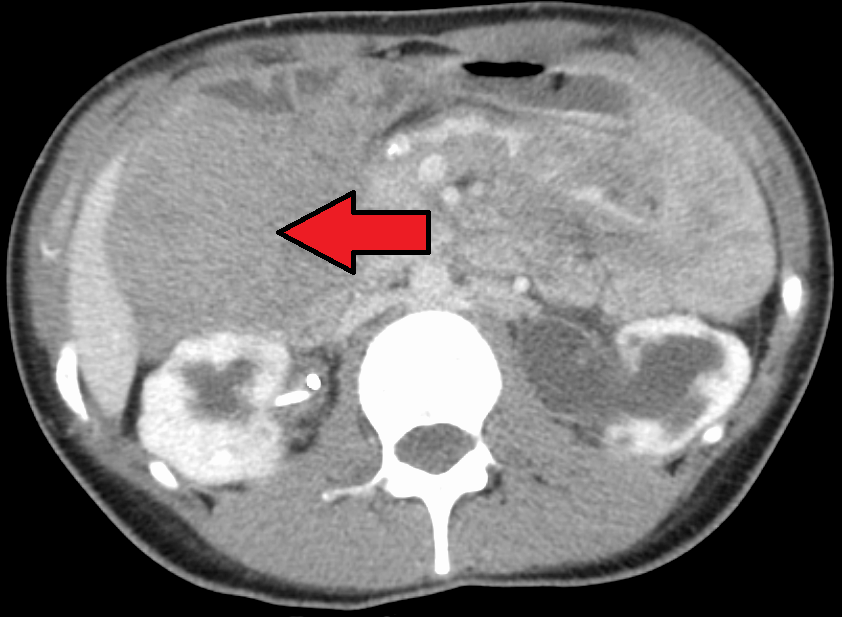

CT 스캔에서 보이는 데스모이드 종양

MRI 또는 CT 스캔 영상 스캔은 일반적으로 모니터링에 사용된다.[47][1]